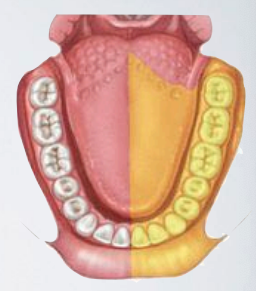

what areas are anesthetized with long buccal nerve block?

Soft tissue and periosteum buccal to the mandibular molar teeth

long buccal nerve block

target area of which nerve block?